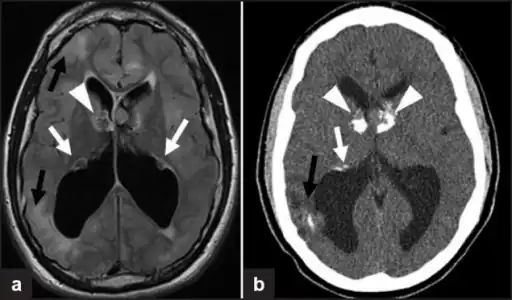

a,b)Images of subependymal giant cell astrocytomas arrowheads

MRI of brain with sub-ependymal giant cell astrocytoma

Diagnosis is made by imaging with a contrast-enhanced MRI or CT scan of the brain.[3]